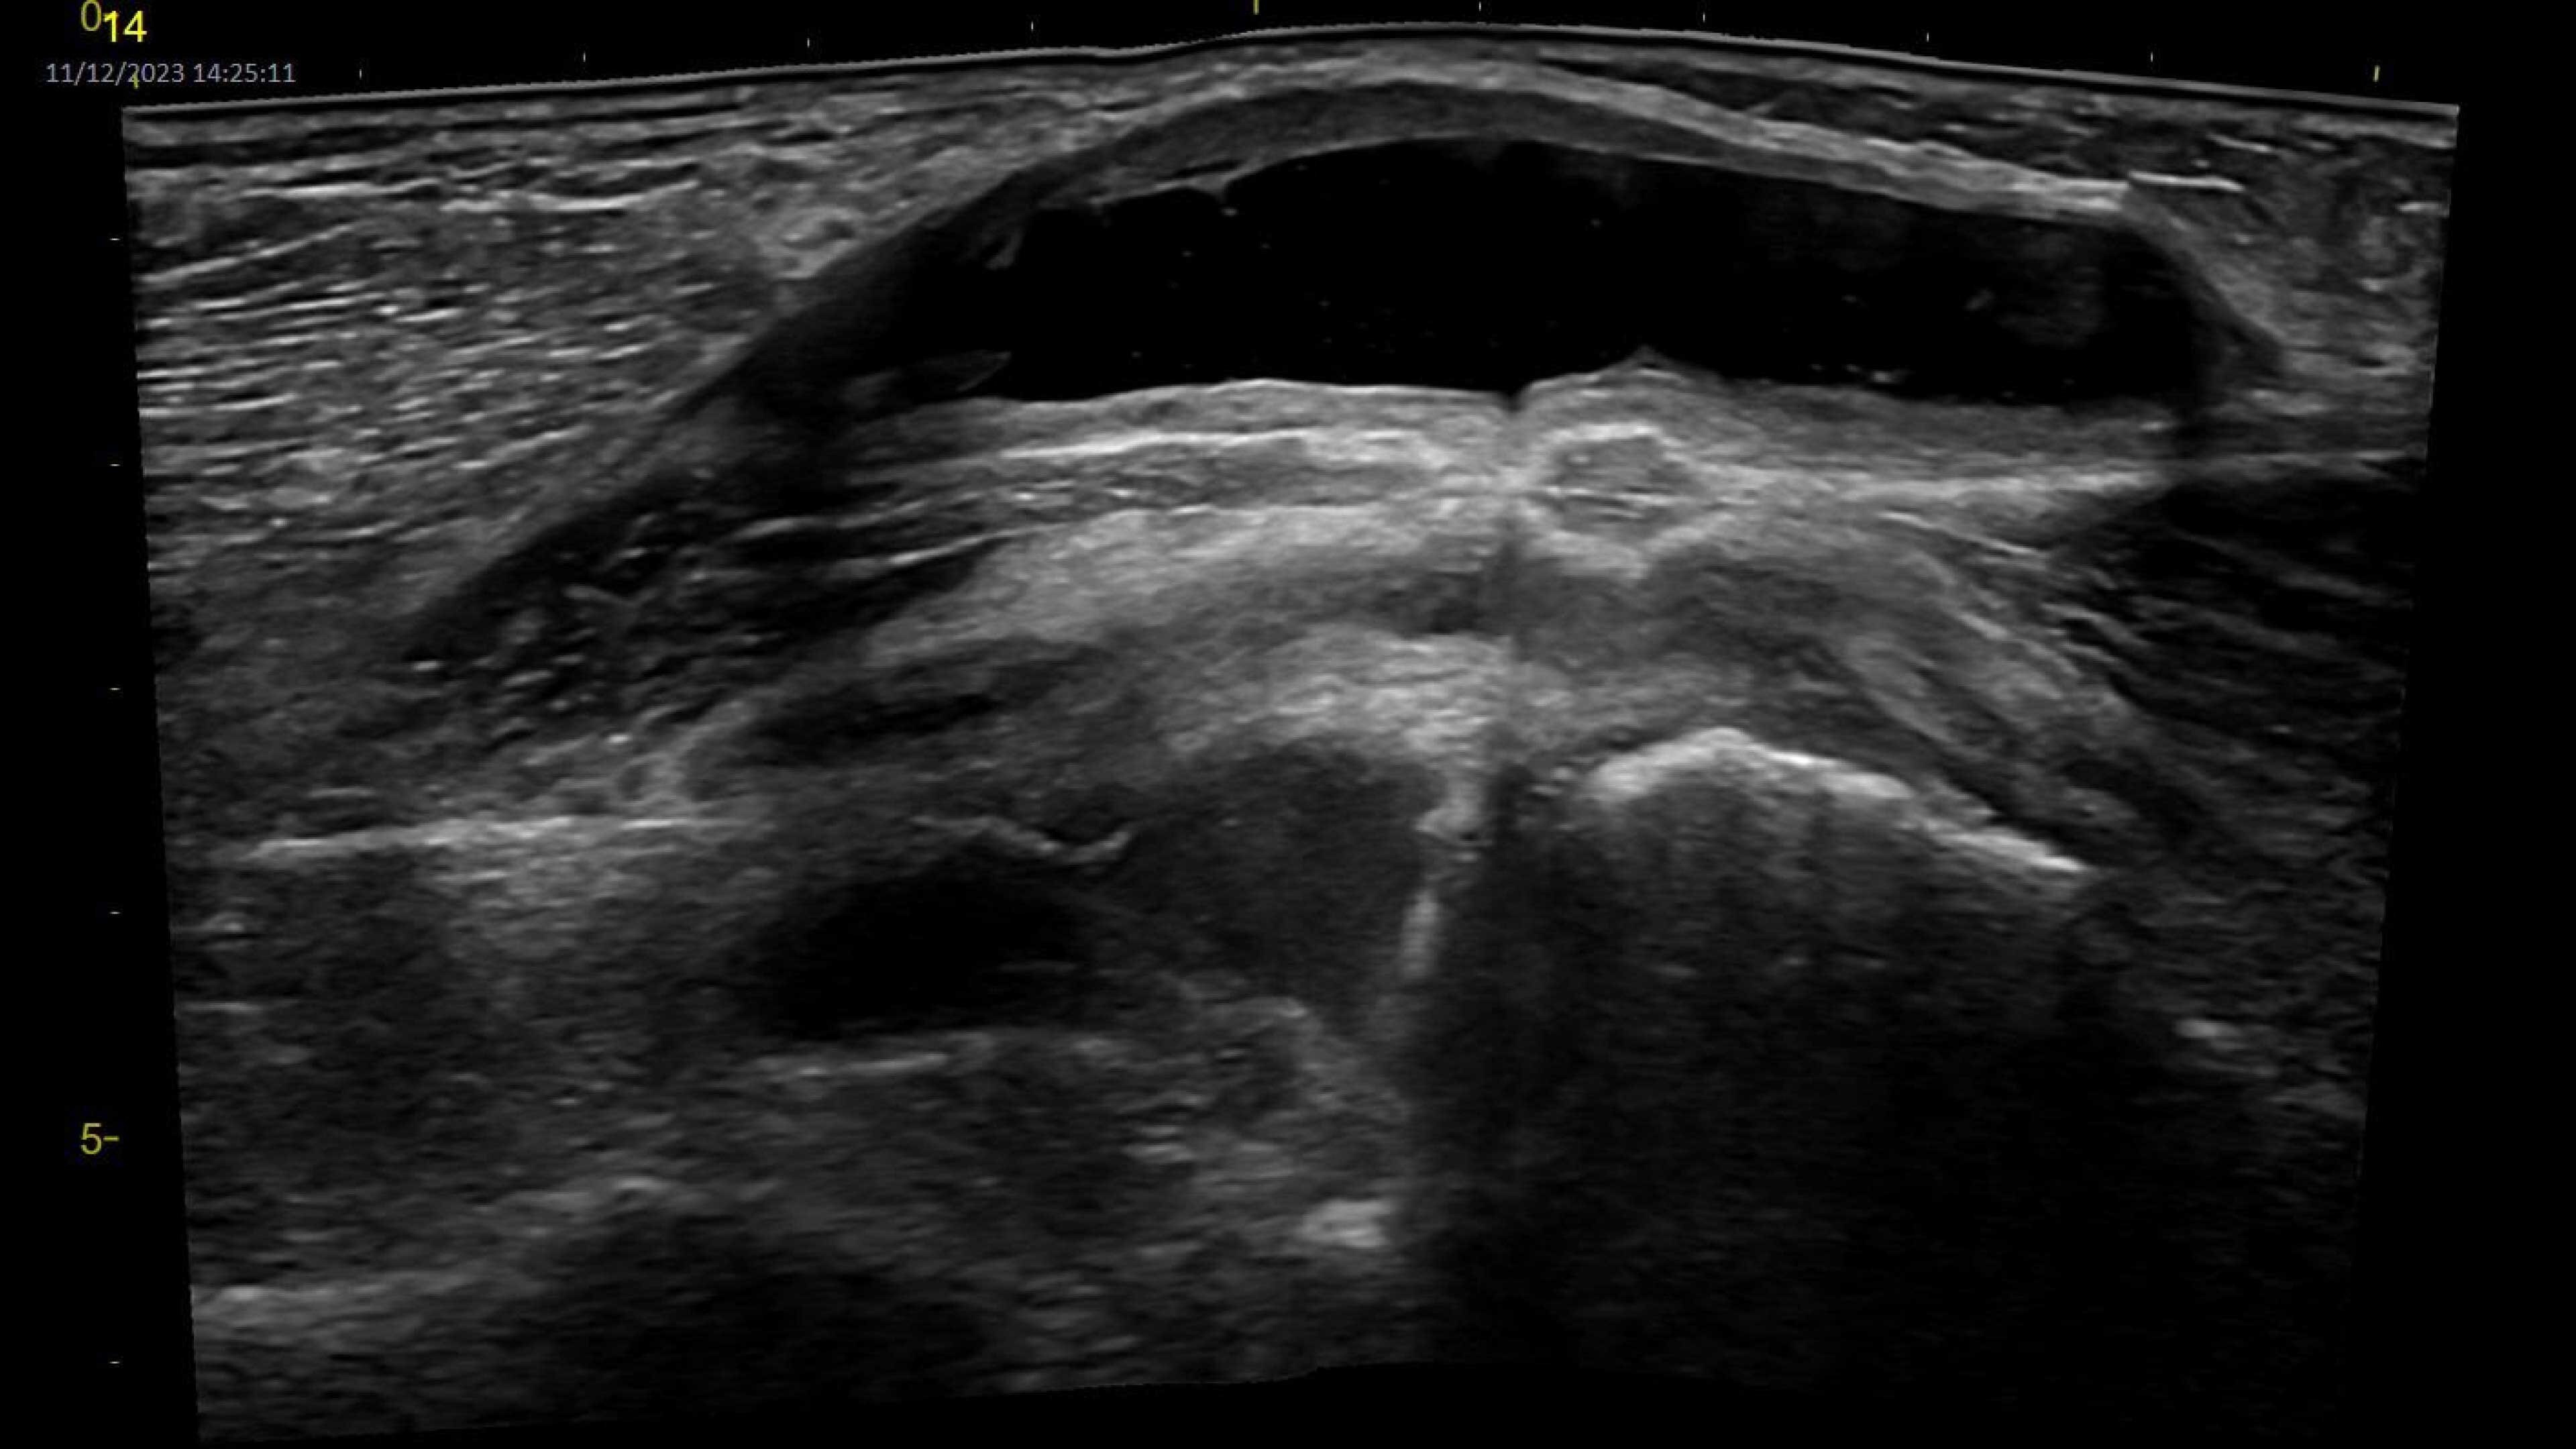

Musculoskeletal (MSK)

A curved array on one side and linear array on the other of the dual wireless probe enables clear assessment of deep and shallow anatomy without switching probes.